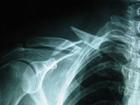

頦孔區骨折:由於頦孔的存在,在解剖學上是個薄弱環節,受到外力時易發生骨折。臨床上多見為單側頦孔區垂直性骨折,下頜骨被分成兩段,後段由於嚼肌、顳肌、翼內肌和下頜舌肌骨的牽引向上、向內移位,而前段由於頦舌骨肌和下頜舌骨肌的牽引向內下方移位,前牙可出現開。

但側頦孔區骨折,骨折線多為垂直。

但側頦孔區骨折,骨折線多為垂直,將下頜骨分成長短不同的2個骨折段,斷骨著片上附著有一側的全部升頜肌(咬肌、翼內肌、顳肌),主要牽拉力使段骨折段向上、向內移。長骨折段與健側下頜骨保持連續,有雙側降頜肌群的牽拉,向下、向後移位並稍偏向患側,同時又以健側關節為支點,骨稍向內旋而使前以出現牙牙合。